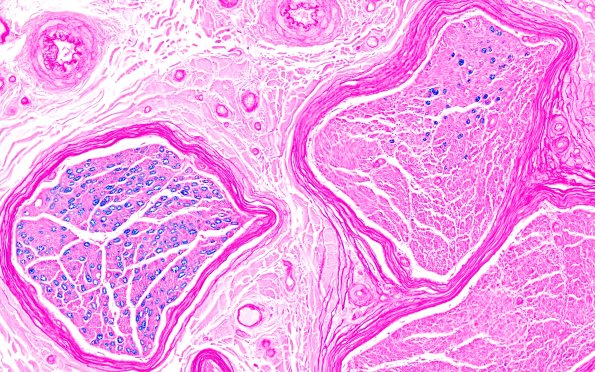

Washington University Experience | PERIPHERAL NEUROPATHY | 11 VASCULITIS - VASCULOPATHY | 3 Vasculitis - NOS | 2B2 (Case 2) LFB 20X 1

2B2,3 Higher magnification image of #2B1 showing variation in axon loss from fascicle to fascicle and within fascicles. (LFB-H&E)